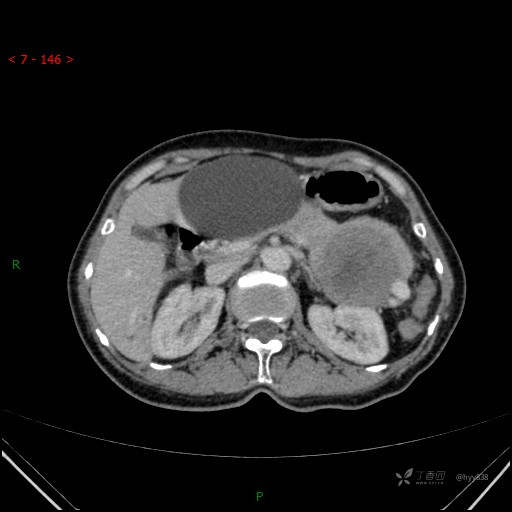

增强静脉期